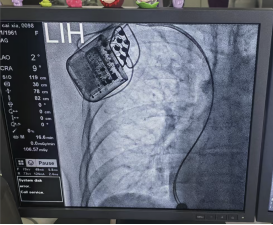

術(shù)中發(fā)現(xiàn)患者右房明顯增大,下腔靜脈增寬,三尖瓣重度返流,導(dǎo)致電極植入困難,在團(tuán)隊(duì)和導(dǎo)管室醫(yī)技人員的密切配合下,先后植入兩根主動起搏電極置于右室間隔。經(jīng)過測試電極各項(xiàng)參數(shù)良好,CCM工作發(fā)送正常,患者各項(xiàng)生命體征平穩(wěn),手術(shù)全程僅40min左右。術(shù)后檢查顯示設(shè)備運(yùn)行良好,患者生命體征平穩(wěn)。